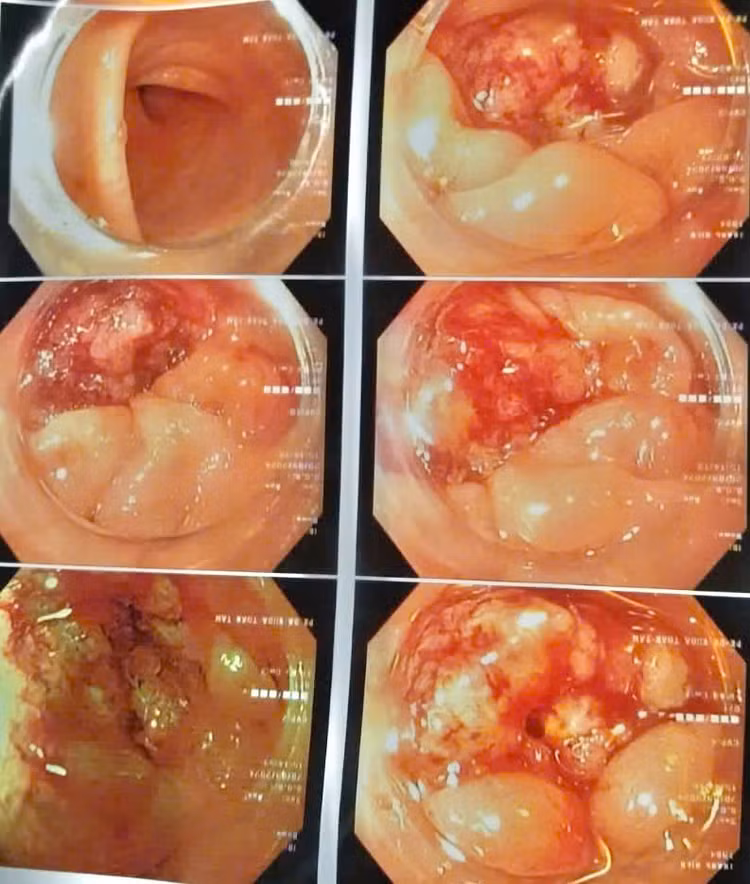

| Hình ảnh tổn thương sùi loét đại tràng qua nội soi. Ảnh BVCC |

Kết quả chụp CT-Scanner ổ bụng và nội soi đại trực tràng cho thấy: xuất hiện nhiều hạch mạc treo đại tràng trái và tổn thương sùi loét đại tràng trái chiếm gần hết chu vi lòng trực tràng.